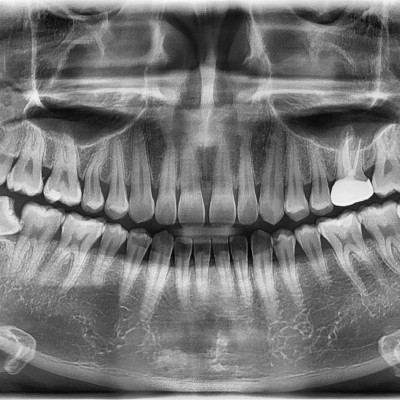

#28,38 사랑니 발치 #28,38 사랑니 발치 구강 외과 전문의가 당일 발치했습니다. --------------------------..

작성자 이턱이 작성일 02-10 조회 50